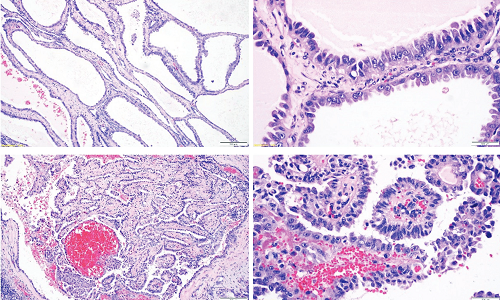

Brain Metastasis of Papillary Ovarian Adenocarcinoma

Sonia Chhabra, Niti Dalal, Sunita Singh

50-52

PDF